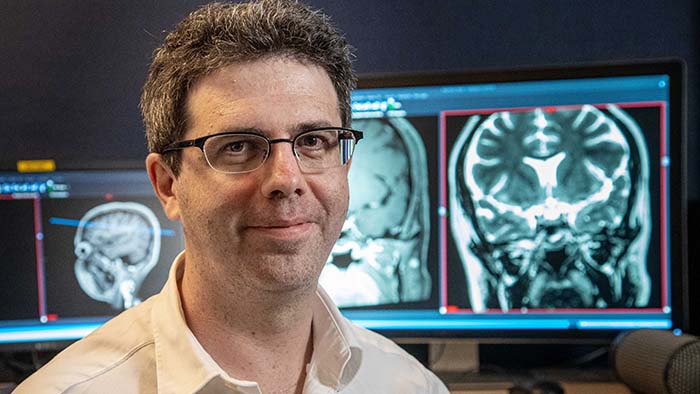

Julien Savatovsky, MD

Diagnostic neuroradiologist at Fondation Rothschild, Paris, since 2006. His clinical interests include advanced diagnostic imaging in neuro, head and neck, and ophthalmology.